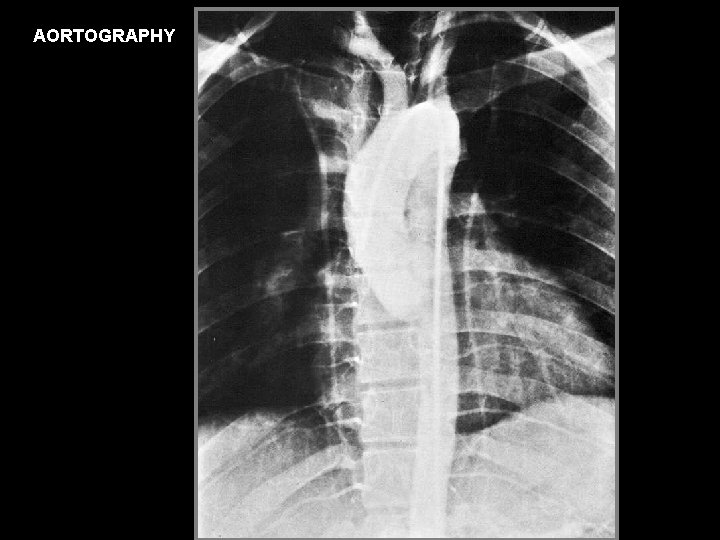

AORTOGRAPHY